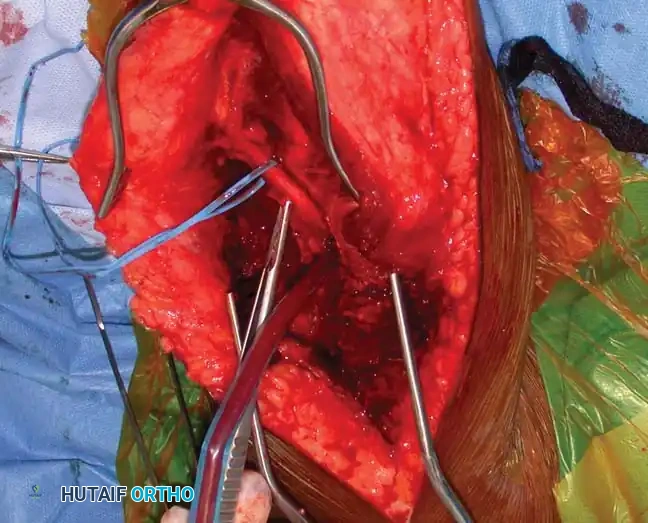

4. Nerve Identification:

* Carefully identify and protect the lateral brachial cutaneous nerve, which serves as a reliable guide to the radial nerve.

Fig. 54-33 C, Identification of the lateral brachial cutaneous nerve.

5. Deep Dissection and Radial Nerve Mobilization:

* Elevate the lateral head of the triceps off the lateral intermuscular septum.

* Identify the radial nerve and the profunda brachii artery as they pierce the lateral intermuscular septum to enter the anterior compartment.

* Carefully mobilize the radial nerve. Use vessel loops for gentle retraction. Never apply excessive traction to the nerve.

Fig. 54-33 D, Mobilization of the radial nerve.